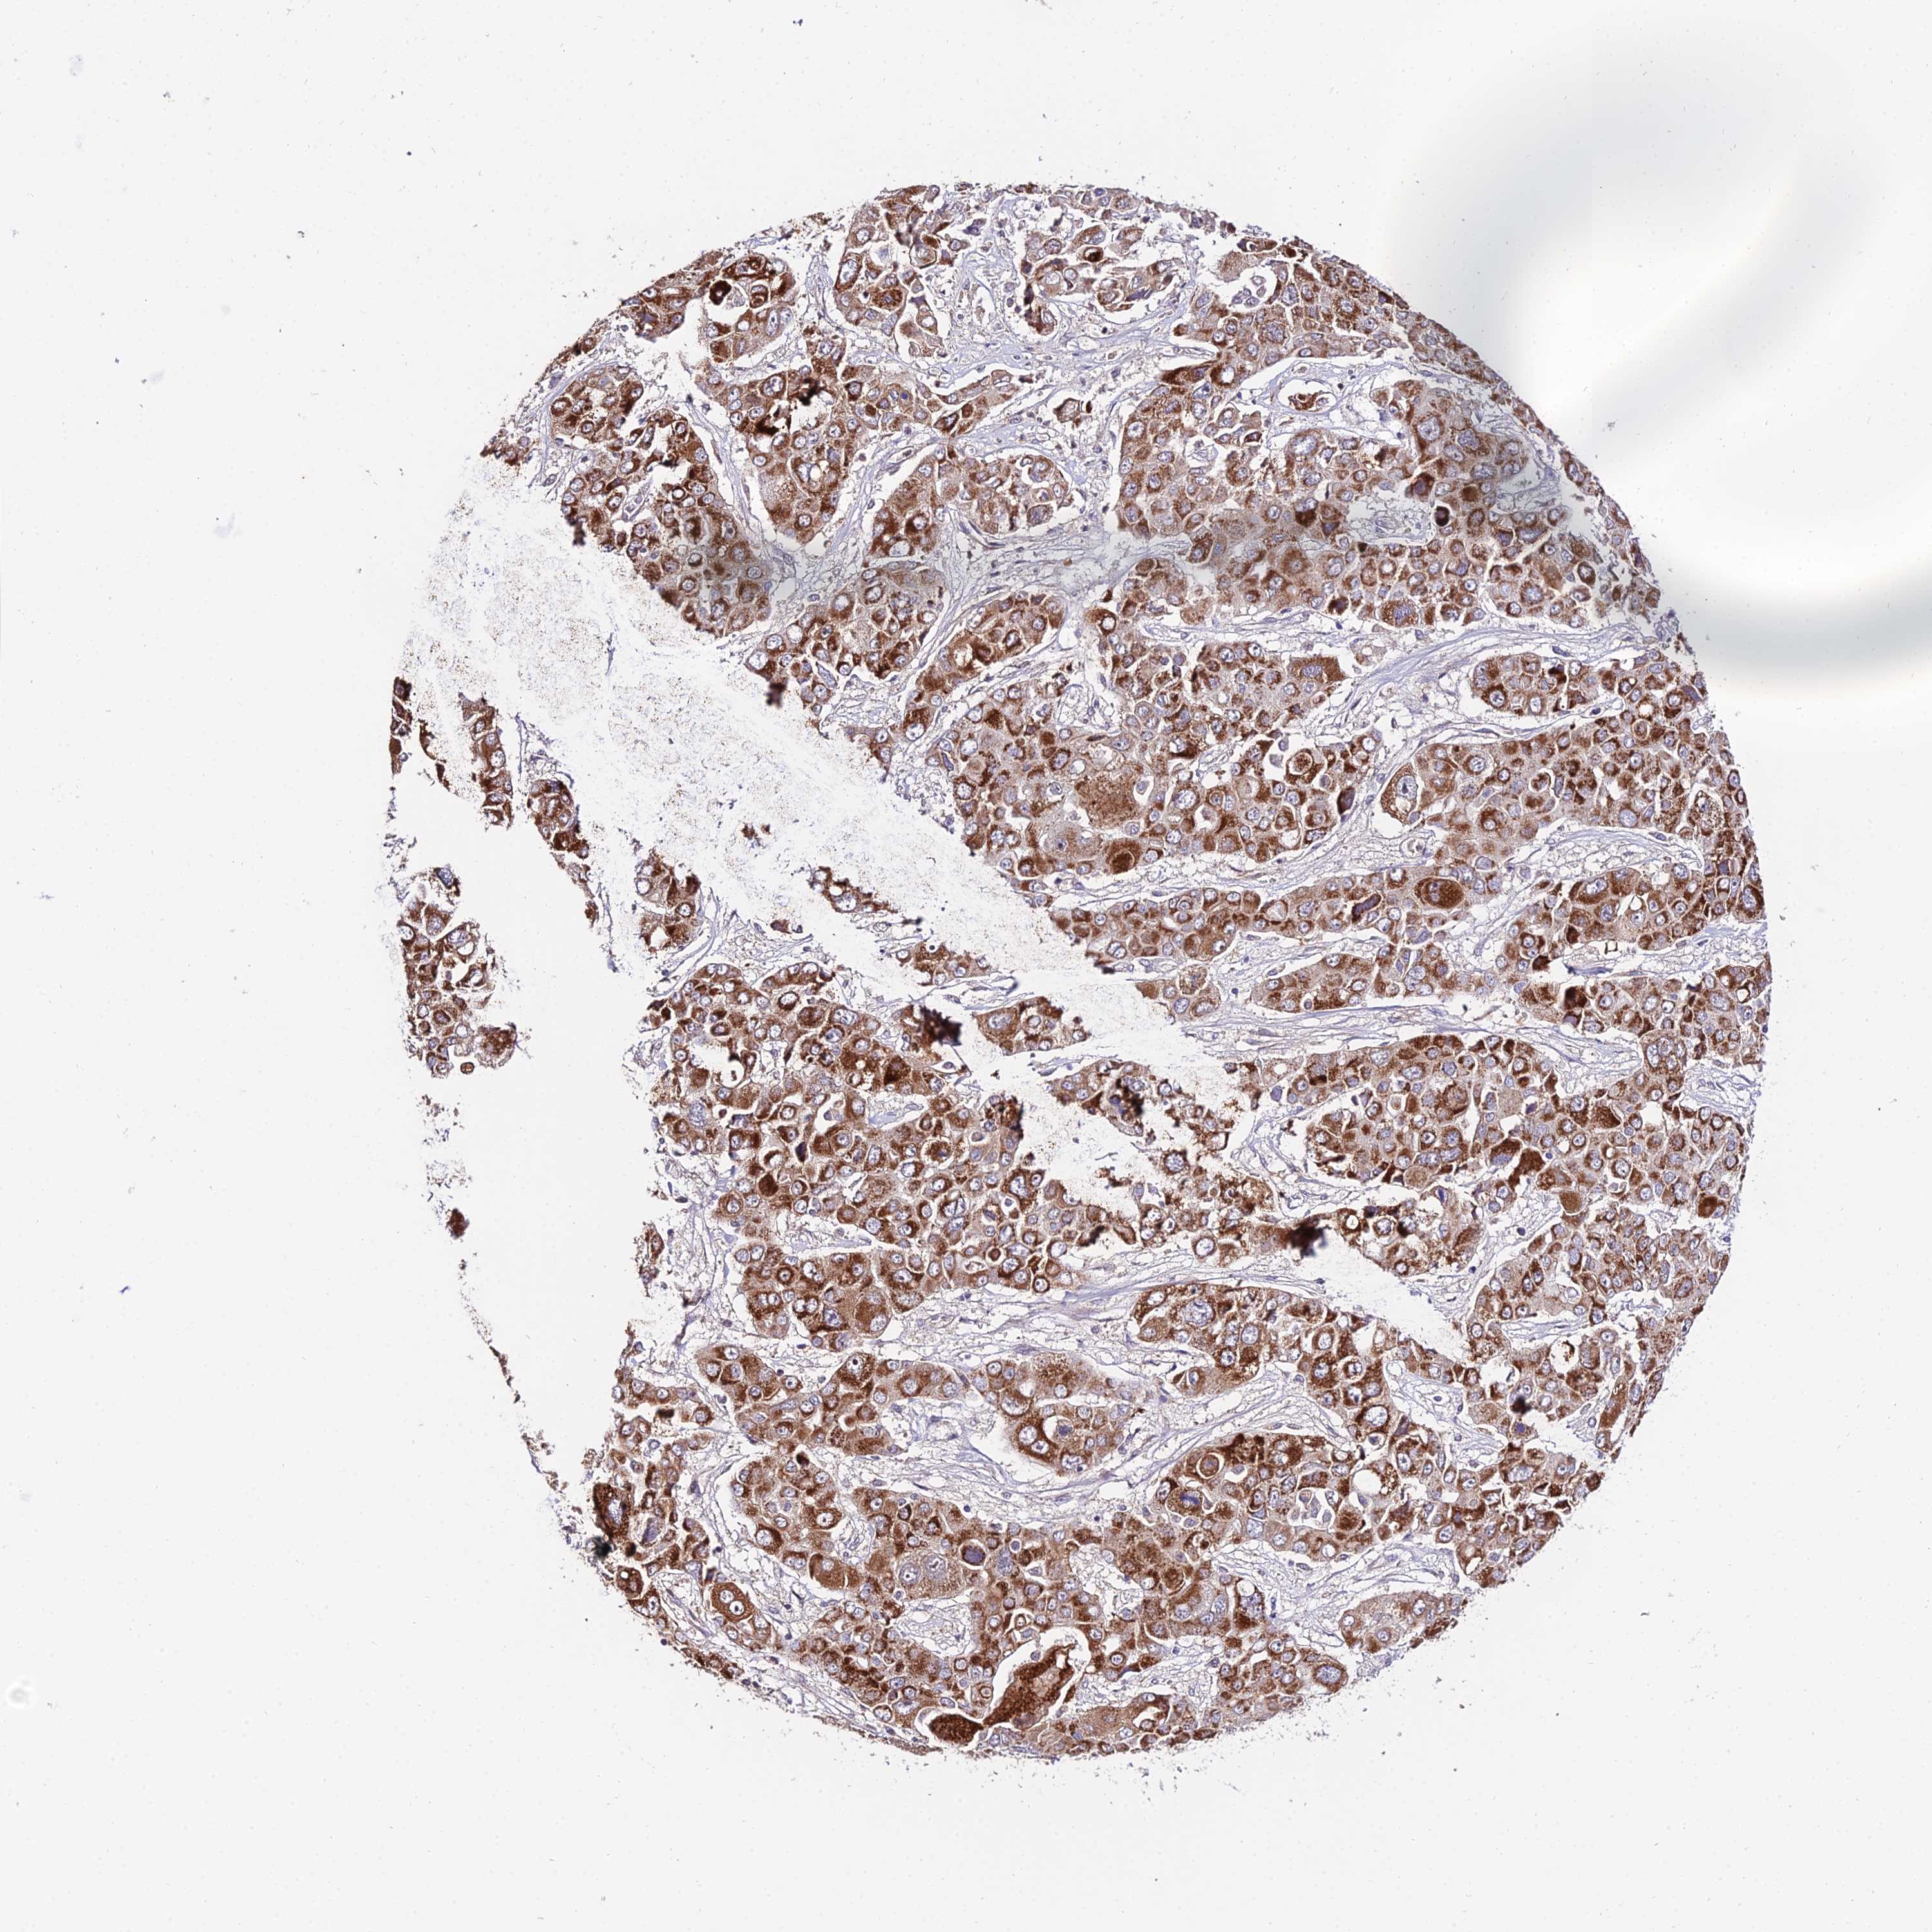

LIVER CANCER - Protein expressioni

A mouse-over function shows sample information and annotation data. Click on an image to view it in a full screen mode. Samples can be filtered based on level of antibody staining by selecting one or several of the following categories: high, medium, low and not detected. The assay and annotation is described here.

Note that samples used for immunohistochemistry by the Human Protein Atlas do not correspond to samples in the TCGA dataset.

Antibody stainingi

Antibody staining in the annotated cell types in the current human tissue is reported as not detected, low, medium, or high, based on conventional immunohistochemistry profiling in selected tissues. This score is based on the combination of the staining intensity and fraction of stained cells.

Each image is clickable and will lead to virtual microscopy that enables deeper exploration of all samples and also displays staining intensity scores, fraction scores and subcellular localization as well as patient and tissue information for each sample.

Antibody HPA042994

Staining

High

Medium

Low

Not detected

Intensity

Strong

Moderate

Weak

Negative

Quantity

>75%

75%-25%

<25%

None

Location

Nuclear

Cytoplasmic/membranous

Cytoplasmic/membranous,nuclear

Cholangiocarcinoma

Carcinoma, Hepatocellular, NOS